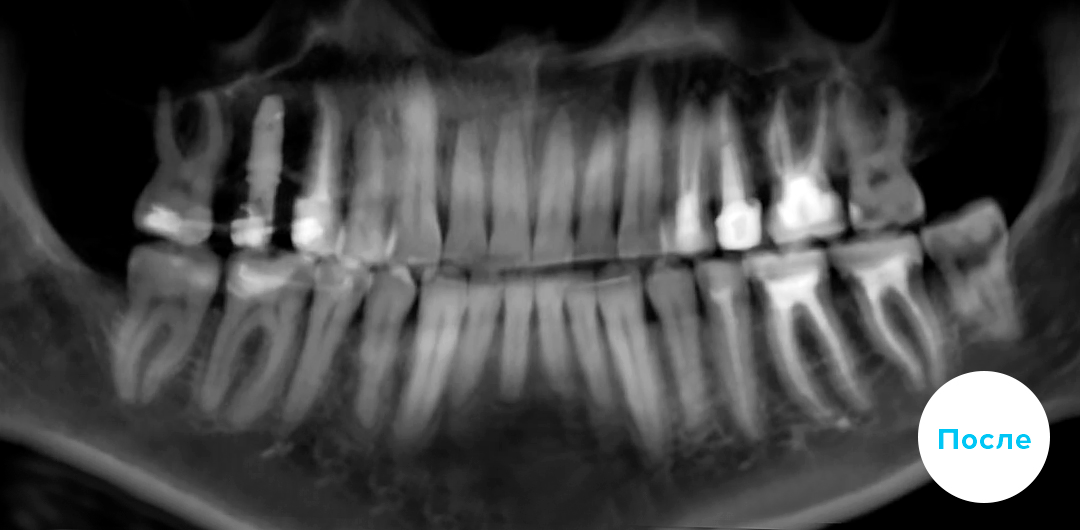

Лечение скученности с последующим протезированием.

Помимо ортодонтии проведено комплексное лечение. Установлен имплантат справа на верхней челюсти. Также пациенту требовался большой объем терапевтического лечения, чтобы привести зубы в порядок.

Пациенту 45 лет

Срок лечения: 21 мес